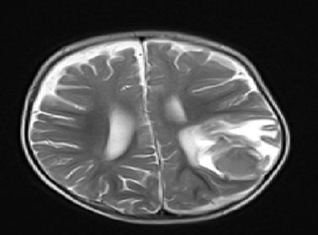

Urinalysis, culture, and sensitivity were normal. PT and APTT were markedly prolonged. The level of the patient revealed a significant decrease of factor V below 1% (normal range 70-120%) and mildly decrease in factor VIII 64% (normal range 70-120%). Other coagulation factors (12,7,9,2,11, von Willebrand factor (VWF) were normal. Lupus anticoagulants were normal. After fresh red blood cell (RBC) and fresh frozen plasma (FFP) were replaced, PT recovered to 13sec and APTT to 30 sec. The patient recovered with FFP and supportive care. After 10 days, on following up the bleeding, magnetic resonance imaging (MRI) was performed and showed bleeding on the mend. (Figure 2).

Figure 2 MRI of the brain showed bleeding on the mend.